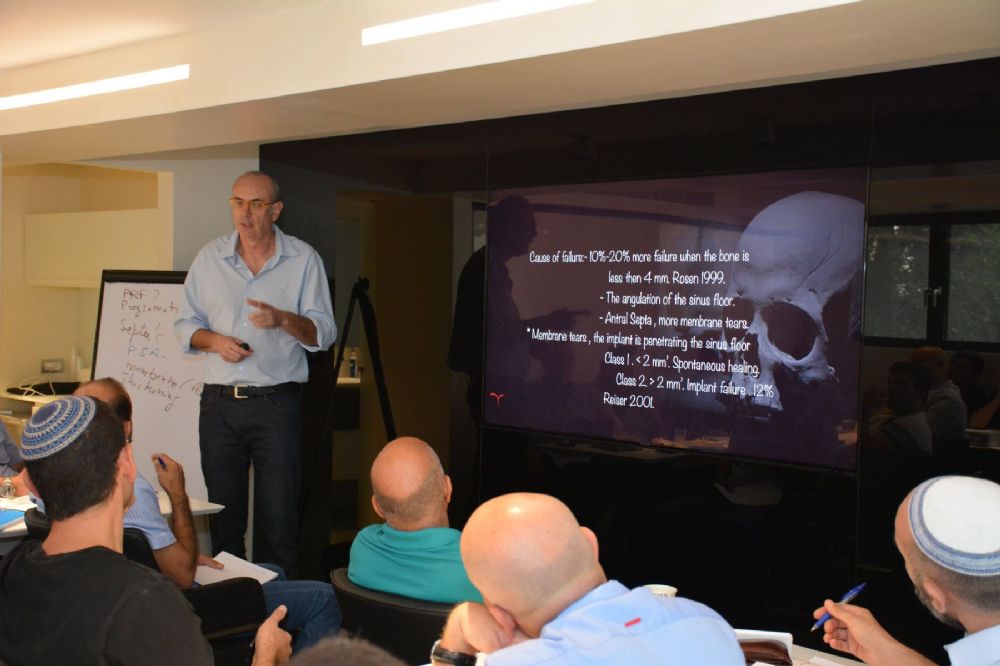

בסמוך למרפאתנו הקמנו חדר הרצאות חדשני וייחודי. ייעודו של האגף החדש הינו להגשים חלום יקר לליבנו, לממש ולקיים מרכז להכשרה קלינית לרופאים ובהדרכה אישית: A PRIVATE ACADEMY. במרכז יתקיימו הרצאות, קורסים עיוניים ומעשיים בהם תהיה צפייה בניתוחים בשידור חי, מחדר הניתוח בזכות מיטב הטכנולוגיה החדשנית. במתחם החדש, אנו נארגן מגוון רב של פעילויות, ומאמינים כי ביכולתנו לתרום מניסיוננו לטובת ציבור רופאי השיניים הכלליים. הקורסים מיועדים לכלל ציבור רופאי השיניים המעוניינים להעשיר את בסיס הידע ואת יכולתם הקלינית בתחומים שונים (פריודונטיה, אימפלנטולוגיה ואסתטיקה), דבר שישרת אותם במרפאתם. המרצים יהיו רופאי המרפאה יחד עם רופאים בכירים ומומחים נוספים אשר יצטרפו לצוות.

קורס עיוני ומעשי | 10-11.1.19

קורס עיוני ומעשי | קורס מס’ 1 | 9-10.11.17

קורס עיוני ומעשי | קורס מס׳ 4 | 10-11.3.16

קורס עיוני ומעשי | קורס מס’ 3 | 22-23.10.15

קורס עיוני ומעשי 29.2-1.3.2024